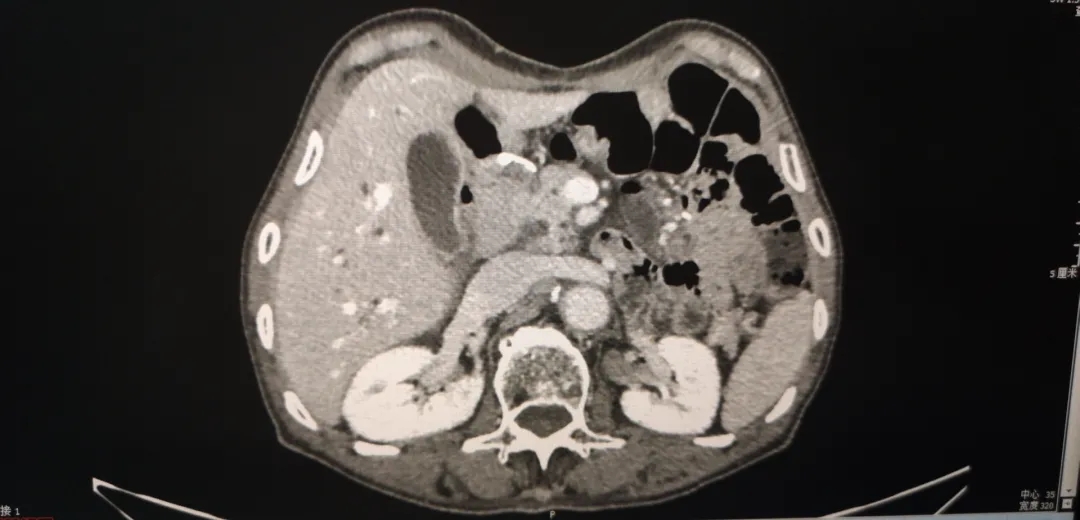

腹盆腔强化CT(2018-4-4):1、胃体及胃窦胃壁增厚,考虑胃癌;2、胃周、胃左动脉区及腹膜后多发肿大淋巴结,考虑转移;3、肝内胆管结石,肝内胆管轻度扩张;4、左肾囊肿,左肾上腺增厚,考虑增生;5、前列腺增生伴钙化;6、盆腔少量积液;7、两下肺实变索条,左侧胸腔少量积液。

图1-1  2018-4-4  箭头为胃周肿大淋巴结

图1-2 2018-4-4 箭头为胃部肿瘤,胃壁增厚明显